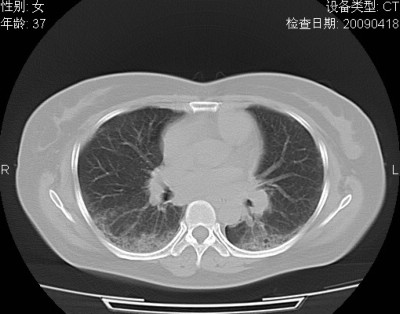

以下是引用随光逐影在2009-4-20 8:03:00的发言:[br]两肺间质性病变(间质性肺炎?特发性肺间质纤维化?)。

以下是引用51736011在2009-4-21 16:24:00的发言:[br]两肺间质性病变(间质性肺炎?特发性肺间质纤维化?)。